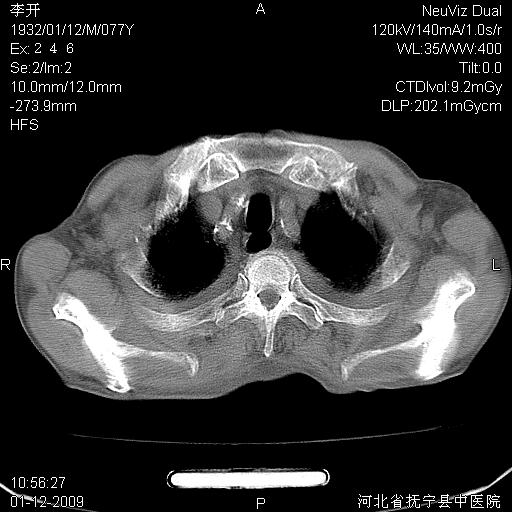

以下是引用黑白光影在2009-1-19 16:49:00的发言:[br]心衰肺水肿;心包、胸腔积液;冠脉钙化;肺部感染。